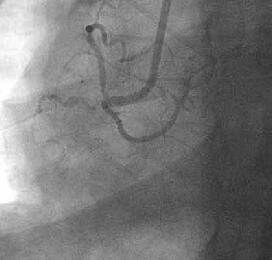

姤摦柆僀儞僞乕儀儞僔儑儞丗僈僀僨傿儞僌僇僥乕僥儖偺engage偑埆偄偨傔丄儔僕

僆僼僅乕僇僗丒儚僀儎乕偱僇僥乕僥儖傪屌掕偝偣側偑傜彊乆偵儚僀儎乕傪恑傔偰

偄偔偲丄彮偟偯偮寣娗偑憿塭偝傟傞傛偆偵側傝丄恖岺寣娗偲LMT偺暙崌晹偵崅搙

嫹嶓傪擣傔傑偟偨乮Figure4乯丅傑偨丄嵍姤摦柆撪偵嫄戝側寣愷傪擣傔傑偟偨丅

摉帪寣愷媧堷偺僨僶僀僗偑側偔丄媧堷偼偱偒傑偣傫偱偟偨丅暙崌晹偵懳偟偰丄

MAVERICK4.0mm偱POBA傪峴偄丄偦偺屻LAD偵嫄戝側寣愷偑棳傟偰偄偔偺偑妋擣偝傟

傑偟偨乮Figure5乯丅NIR4mm僗僥儞僩傪棷抲偟暙崌晹嫹嶓偼夵慞偟傑偟偨偑丄LAD

偺no flow傪擣傔傑偟偨丅nicorandil偍傛傃UK傪姤拲偟偨偲偙傠丄flow偑夵慞偟

偨偨傔庤媄傪廔椆偟傑偟偨乮Figure6乯丅